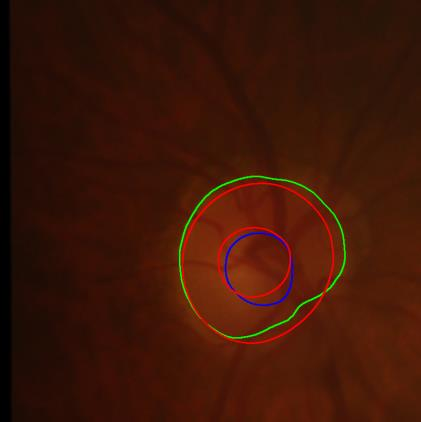

Modern deep neural networks struggle to transfer knowledge and generalize across diverse domains when deployed to real-world applications. Currently, domain generalization (DG) is introduced to learn a universal representation from multiple domains to improve the network generalization ability on unseen domains. However, previous DG methods only focus on the data-level consistency scheme without considering the synergistic regularization among different consistency schemes. In this paper, we present a novel Hierarchical Consistency framework for Domain Generalization (HCDG) by integrating Extrinsic Consistency and Intrinsic Consistency synergistically. Particularly, for the Extrinsic Consistency, we leverage the knowledge across multiple source domains to enforce data-level consistency. To better enhance such consistency, we design a novel Amplitude Gaussian-mixing strategy into Fourier-based data augmentation called DomainUp. For the Intrinsic Consistency, we perform task-level consistency for the same instance under the dual-task scenario. We evaluate the proposed HCDG framework on two medical image segmentation tasks, i.e., optic cup/disc segmentation on fundus images and prostate MRI segmentation. Extensive experimental results manifest the effectiveness and versatility of our HCDG framework.